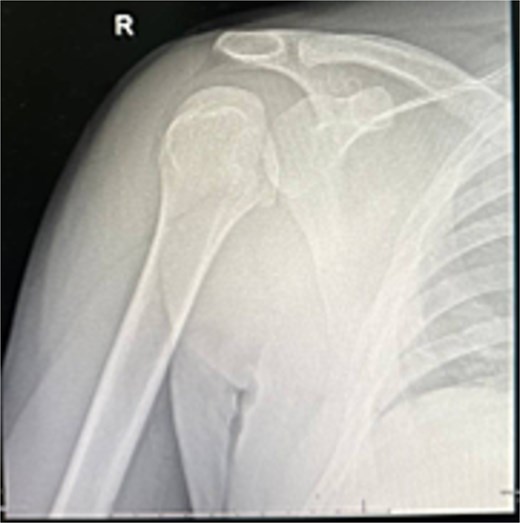

He was counseled for open reduction and modified McLaughlin procedure. Through a deltopectoral approach, open reduction was achieved, and subscapularis with lesser tuberosity was transferred to the defect and fixed with a partially threaded screw. Postoperative X-rays showed satisfactory reduction (Fig. 3). He was discharged the next day in an external rotation brace.